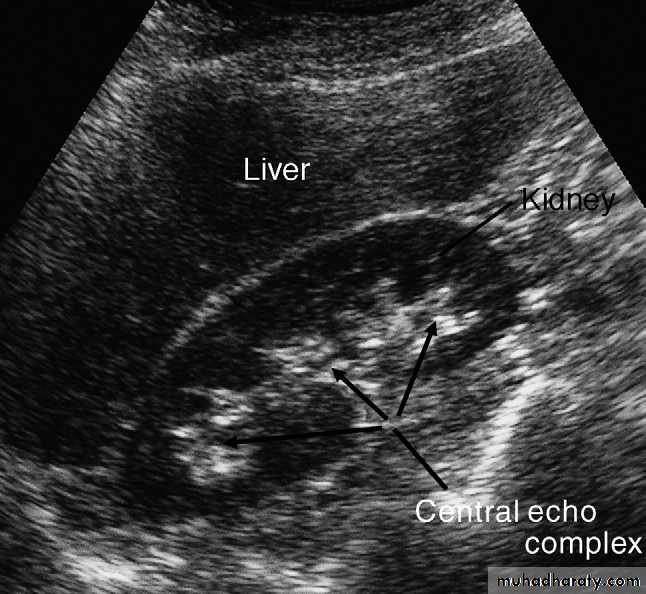

Normal renal ultrasound

At ultrasound, the kidneys should be smooth in outline. The parenchyma surrounds a central echo-dense region, known as the central echo complex (the renal sinus), consisting of the pelvicaliceal system, together with the surrounding fat and renal blood vessels .

In most instances, the normal pelvicaliceal system is not visible within the renal sinus.

The normal adult renal length, measured by ultrasound,is 9–12 cm. Renal length varies with age, being maximal in the young adult. There may be a difference between the two kidneys, normally of less than 1.5 cm.Normal ureters are not usually visualized due to overlying bowel gas.